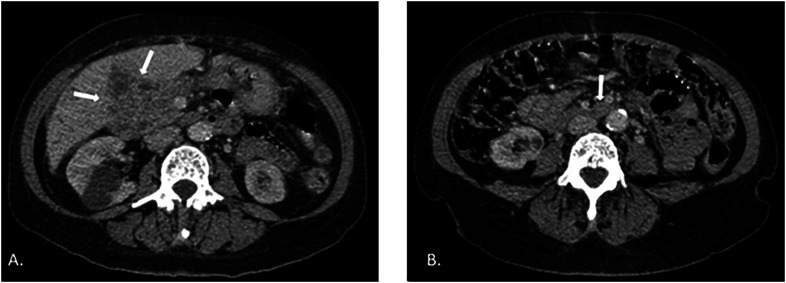

副球孢子菌病是拉丁美洲最重要的全身性真菌病,与农村活动密切相关。在巴西,它是一种地方病,估计每年有 4000 到 6000 个病例,占全球诊断病例的 80% 以上。我们介绍了一例罕见的病例,患者是一名 71 岁的妇女,以肠道表现为主。盲肠阑尾受累导致了胆管炎并发症,其症状与胆管癌相似。

Paracoccidioidomycosis, the most important systemic mycosis in Latin America, is closely linked to rural activities. In Brazil, it is an endemic disease, with an estimated 4,000 to 6,000 annual cases, accounting for over 80% of the global diagnoses. We present an intriguing case of this disease with an intestinal manifestation in a 71-year-old woman. The involvement of the cecal appendix led to a complication of cholangitis that mimicked cholangiocarcinoma.